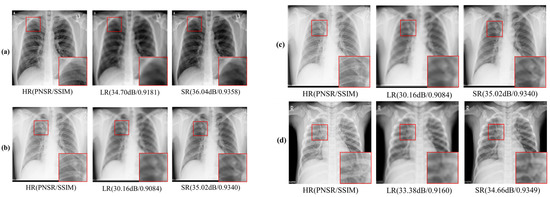

4. Experiments and Results

4.3. Classification Evaluation